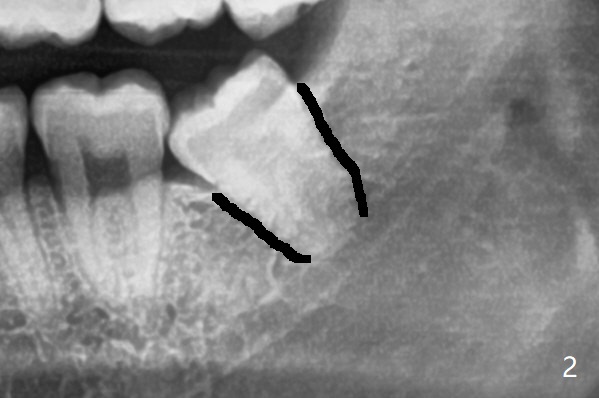

下牙槽神经管(*)位于智齿根尖下方(图一);一种拔除智齿方法是颊侧沟形成后,尽量松动智齿,包括牙根,在牙根周围形成空间(图二:黑色)